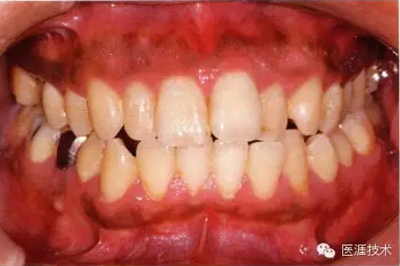

55歲牙周炎男性的臨床照片

上海品瑞邁格磁致伸縮治療儀

55歲男性抽煙患者(1天20支、抽煙35年)。菌斑控制得不好。通過牙周探診,全頜有4~9mm的牙周袋,有1~3度的根分叉部病變。通過X光片觀察,上頜前牙中度牙槽骨吸收,其他地方有中度牙槽骨吸收。受吸煙影響,牙齦纖維性肥厚,呈紅黑色。牙齦幾乎沒有浮腫和發(fā)紅,所以這個病例是從外觀上無法預測病癥嚴重程度的病例。